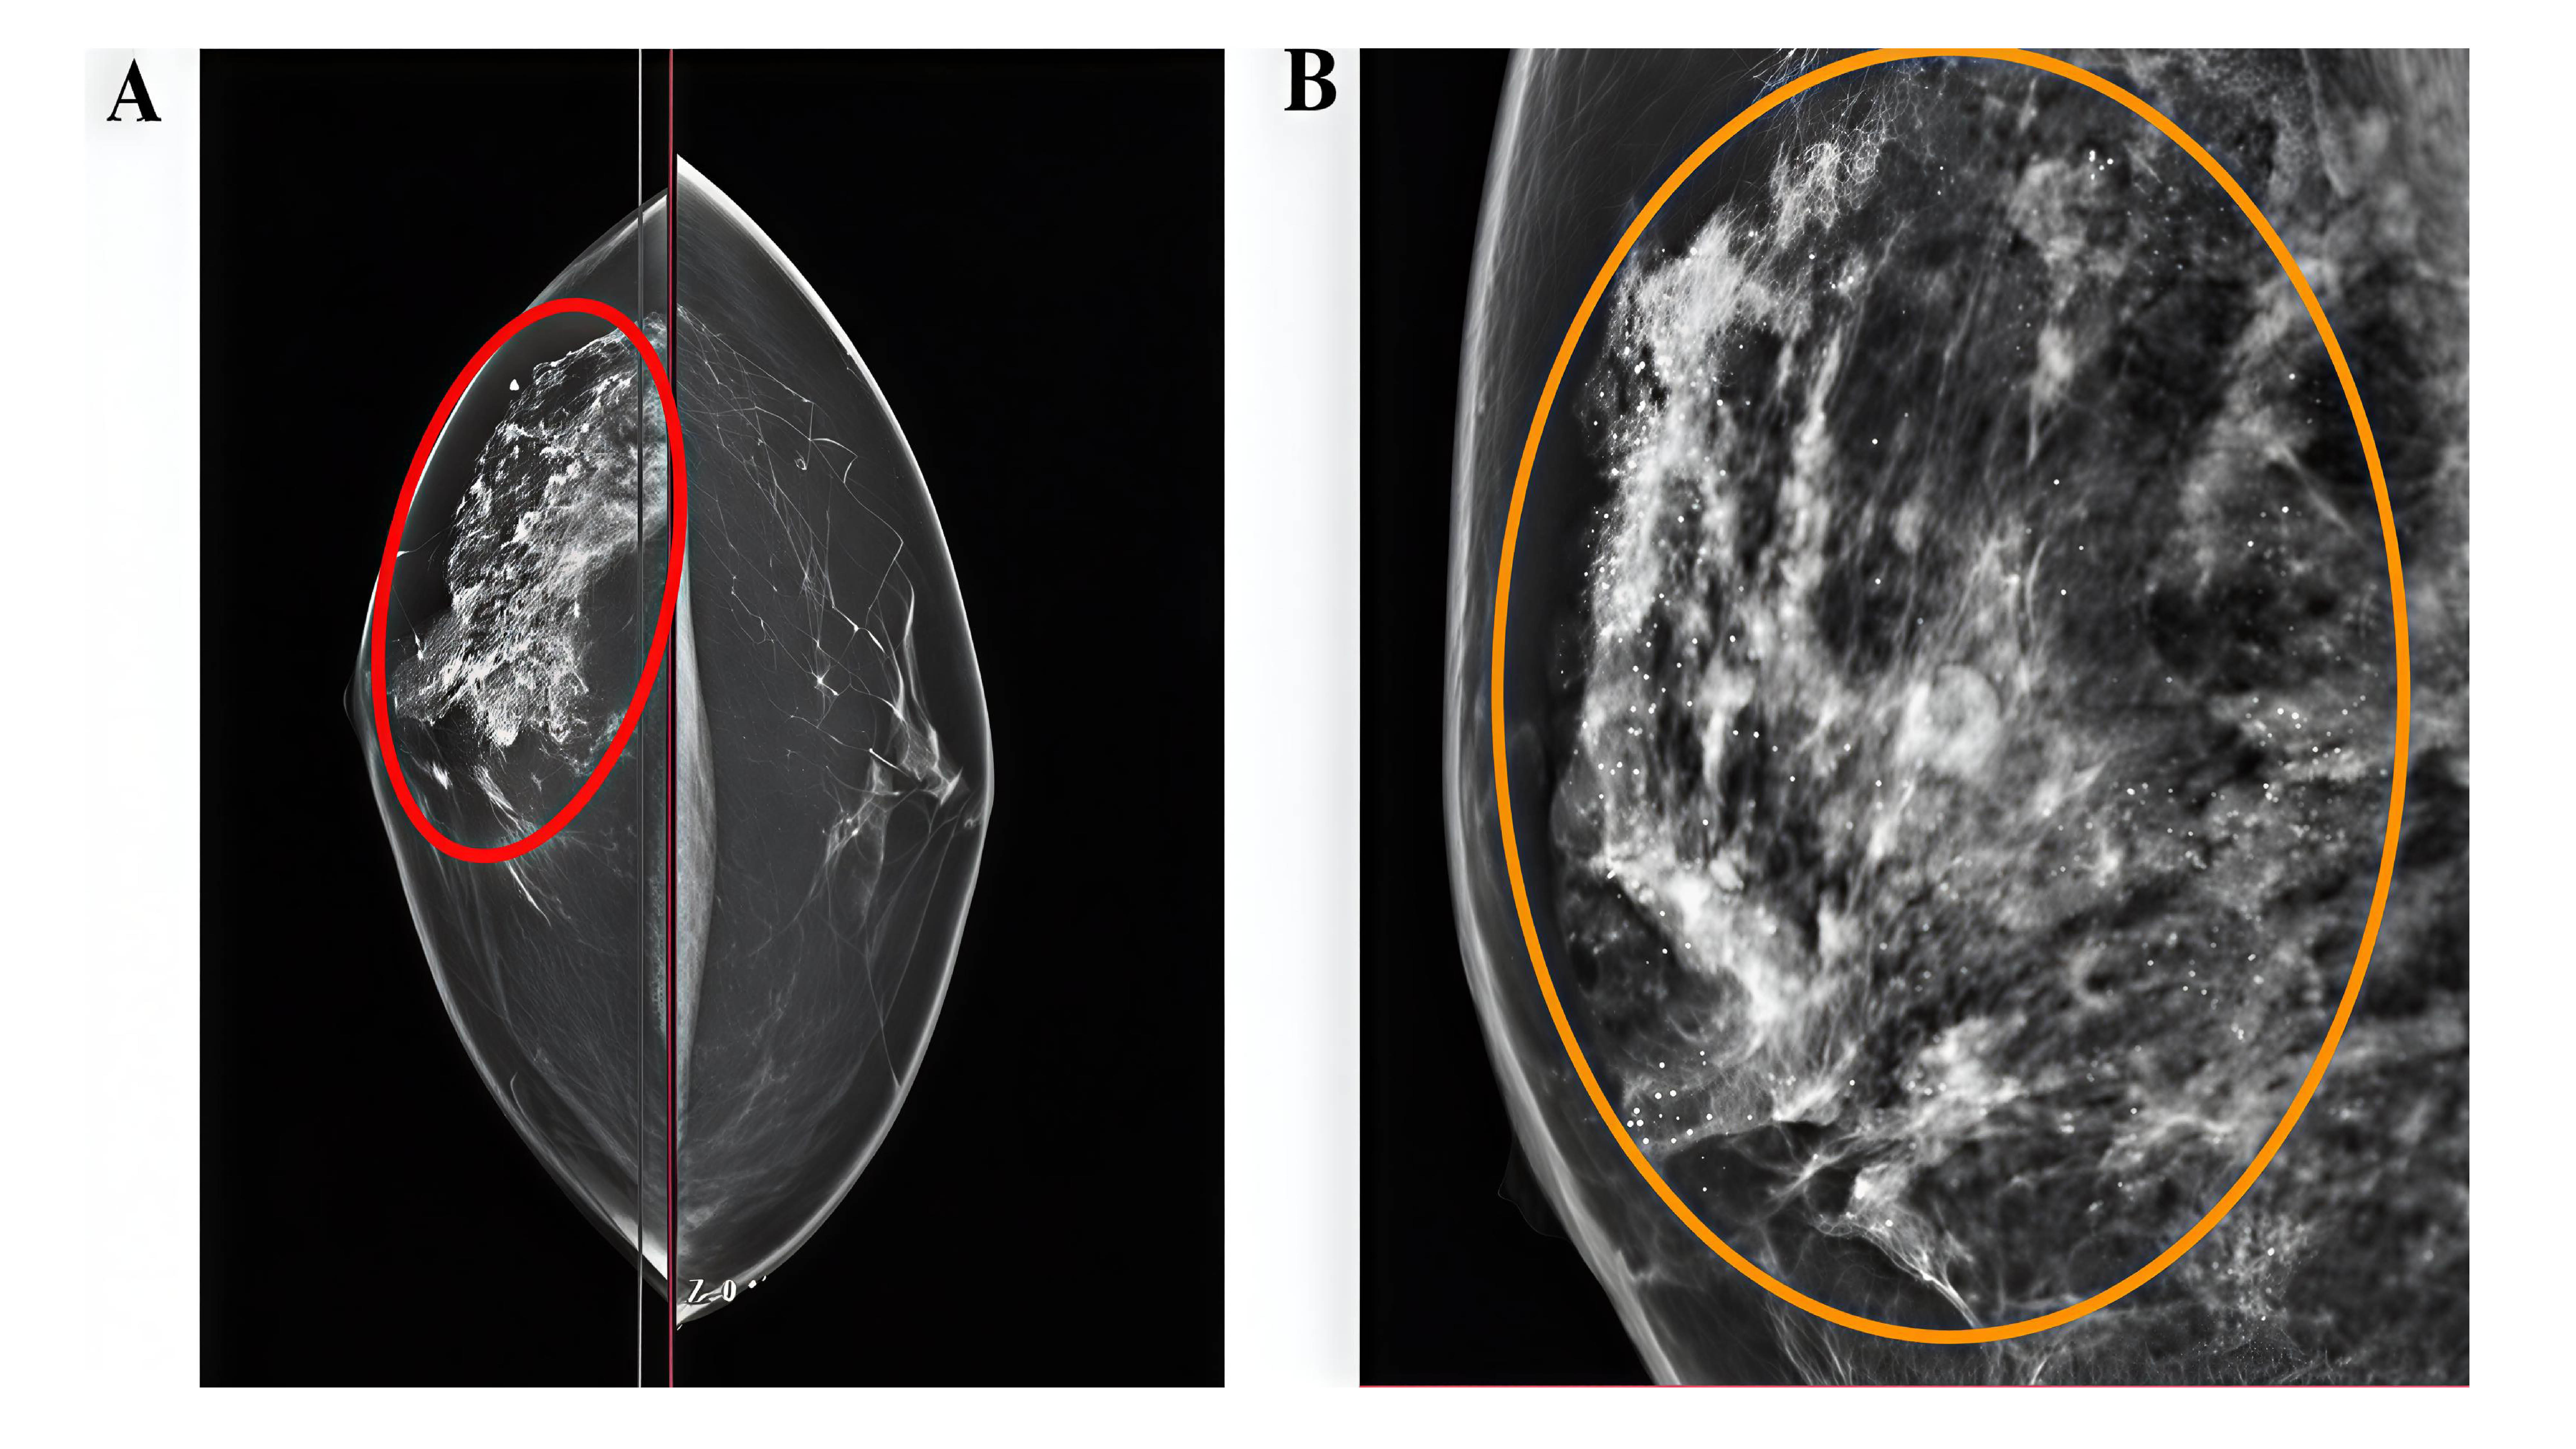

Fahmi H. Kakamad, Berun A. Abdalla, Dahat A. Hussein, Fakher Abdullah, Ayman M. Mustafa, Sabah J. Hasan, Mohammed S. Ezzat, Harem S. Amin, Lanya Q. Rashid, Muhammad A. Khdir, Danyar G. HamaSaeed, Hussein H. Rasul, Akam R. Ahmed (Author)

DOI: https://doi.org/10.70955/JCJ.2025.12

First Published : 2025-11-18

Page 89-98